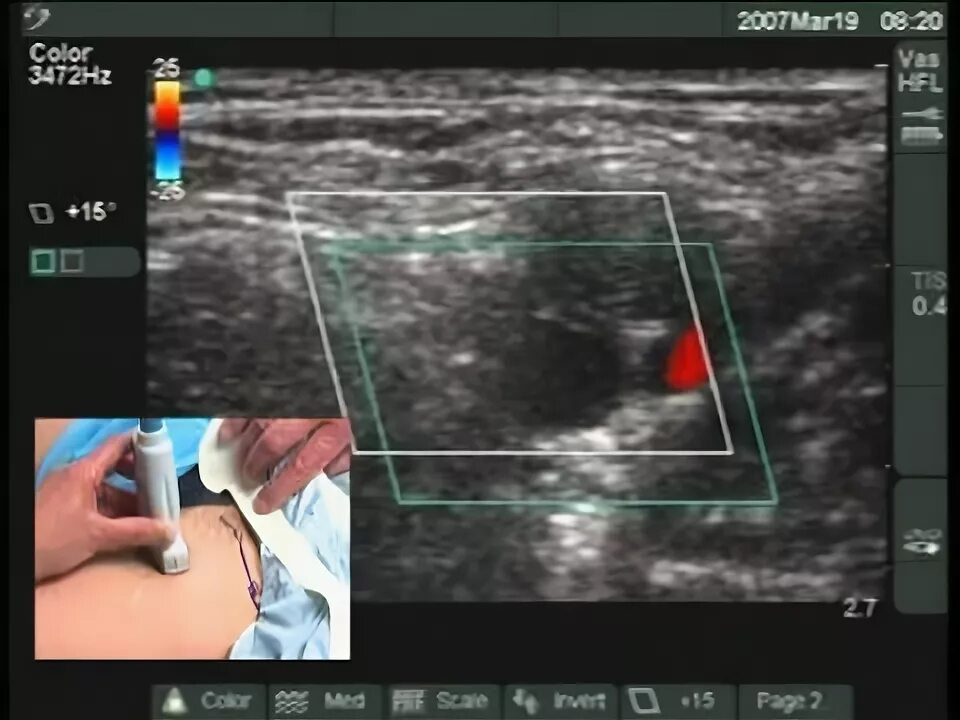

Узи нервов сделать в москве